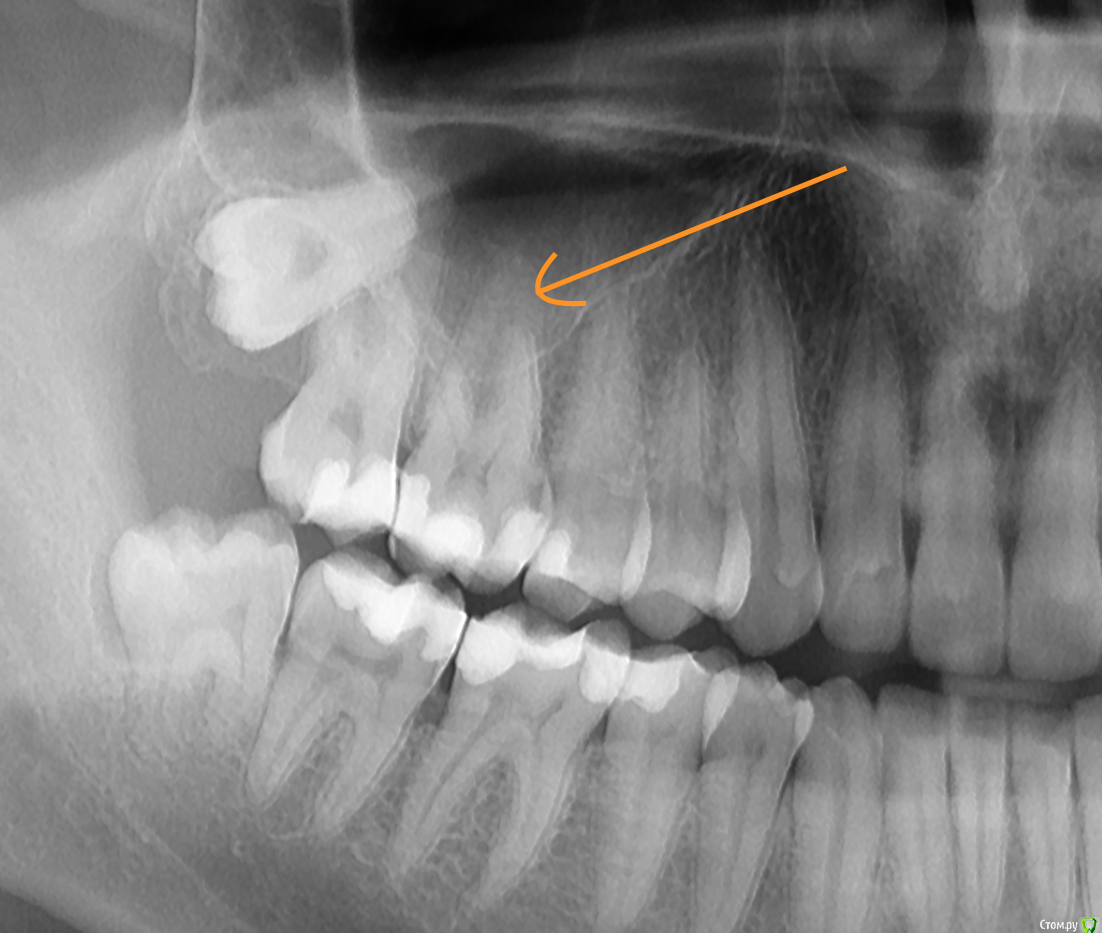

Руслан81 Опубликовано 5 октября, 2017 Поделиться Опубликовано 5 октября, 2017 Шестерка-верхняя челюсть. Провели пломбировку каналов после пульпита. Пульпит упорно не видели, пока не сделали 3Д. До этого запломбировали живой зуб , но чувствительность не уходила. После диагностики по 3Д увидели старый пульпит, удалили нервы и запломбировали каналы. При пломбировке один канал кровоточил, ждали неделю с лекарством, только после этого провели пломбировку.Через месяц после пломбировки у зуба появилась чувствительность, отличная от других зубов. Боли нет, но ощущения неприятные. При нажатии ничего нет, при постукивании неприятное ощущение-не боль.Хотел бы узнать правильно ли и до конца ли запломбированы каналы (по фото).До ремонта зуба была парестезия с этой же стороны по ходу 1-й ветви тройничного нерва. Все врачи-невропатологи, в том числе зарубежные, ничего по части неврологии не нашли. Эта парестезия прошла после удаления нервов зуба, но вот месяц спустя вернулась вместе с чувствительностью 6-ки. Или может это вообще связано с 8-кой которая там лежит почти в полости гайморовой пазухи и даже не показывается?Спасибо за любые комментарии. Ссылка на комментарий

kramer Опубликовано 5 октября, 2017 Поделиться Опубликовано 5 октября, 2017 Я бы сначала удалил 8, дальше по ситуации 2 Ссылка на комментарий

krokomot Опубликовано 5 октября, 2017 Поделиться Опубликовано 5 октября, 2017 http://http://s019.radikal.ru/i639/1710/da/f5e5ba37932d.pngканалы запломбированы до верхушек в 6-ом зубе, но вопросы к 7-ому 2 Ссылка на комментарий

Руслан81 Опубликовано 5 октября, 2017 Автор Поделиться Опубликовано 5 октября, 2017 (изменено) Спасибо за ответы! В 7-м ничего не болит, но он упирается в 8-ку (верхнюю), которую удалять нужно только с открытием гайморовой пазухи. Стоматолог ничего вразумительного сказать не может по этому вопросу. Изменено 5 октября, 2017 пользователем Руслан81 Ссылка на комментарий

Руслан81 Опубликовано 5 октября, 2017 Автор Поделиться Опубликовано 5 октября, 2017 (изменено) Я бы сначала удалил 8, дальше по ситуацииДо него так просто не добраться по словам ЛОРа верхняя 8-ка лежит в пазухе и никак себя не проявляет. Чтобы ее удалить нужно вскрывать пазуху.Нижнюю удалил на прошлой неделе. Изменено 5 октября, 2017 пользователем Руслан81 Ссылка на комментарий

Руслан81 Опубликовано 5 октября, 2017 Автор Поделиться Опубликовано 5 октября, 2017 каналы запломбированы до верхушек в 6-ом зубе, но вопросы к 7-ому а что с 7-м? Ссылка на комментарий

shishok Опубликовано 5 октября, 2017 Поделиться Опубликовано 5 октября, 2017 а что с 7-м? Близкое расположение пульпы к дну кариозной полости. 1 Ссылка на комментарий